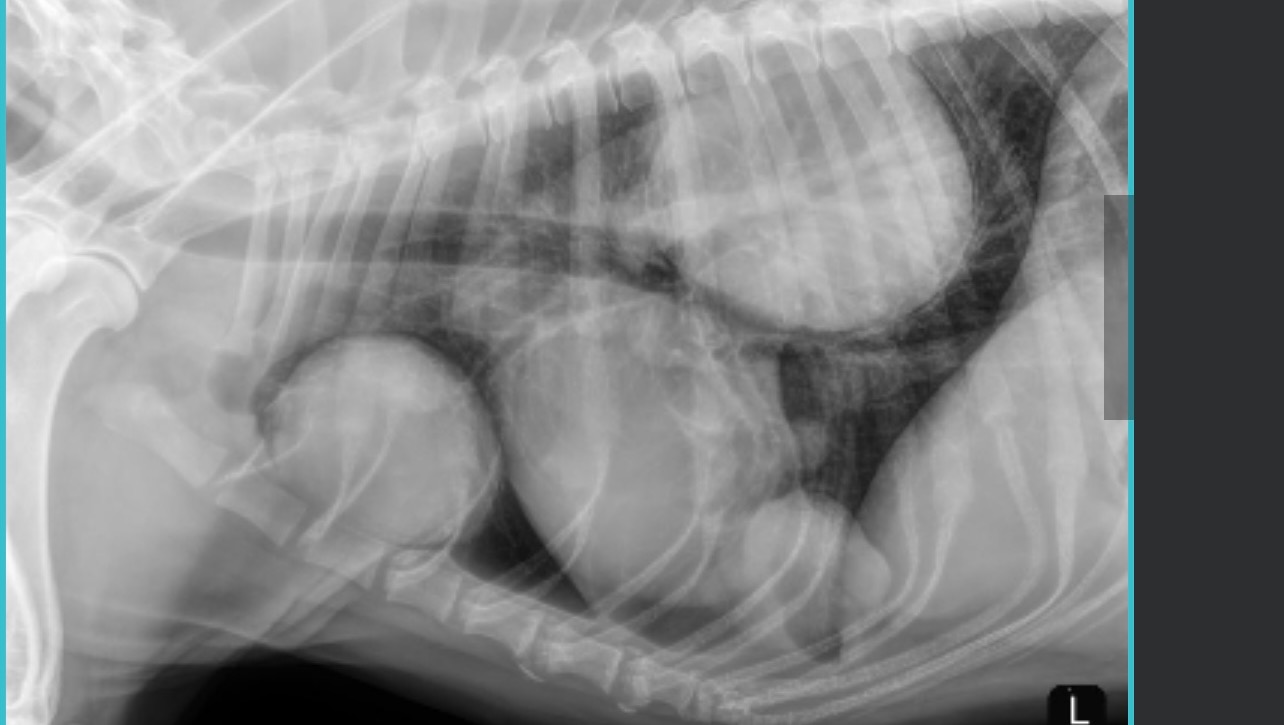

On Saturday, July 6th, my heart shattered when I had to rush Nala to the emergency vet. Her legs were swollen and she could barely walk. After extensive tests and X-rays, the devastating news came. The vet found three large tumors pressing against her lungs and heart, making it hard for her to breathe.